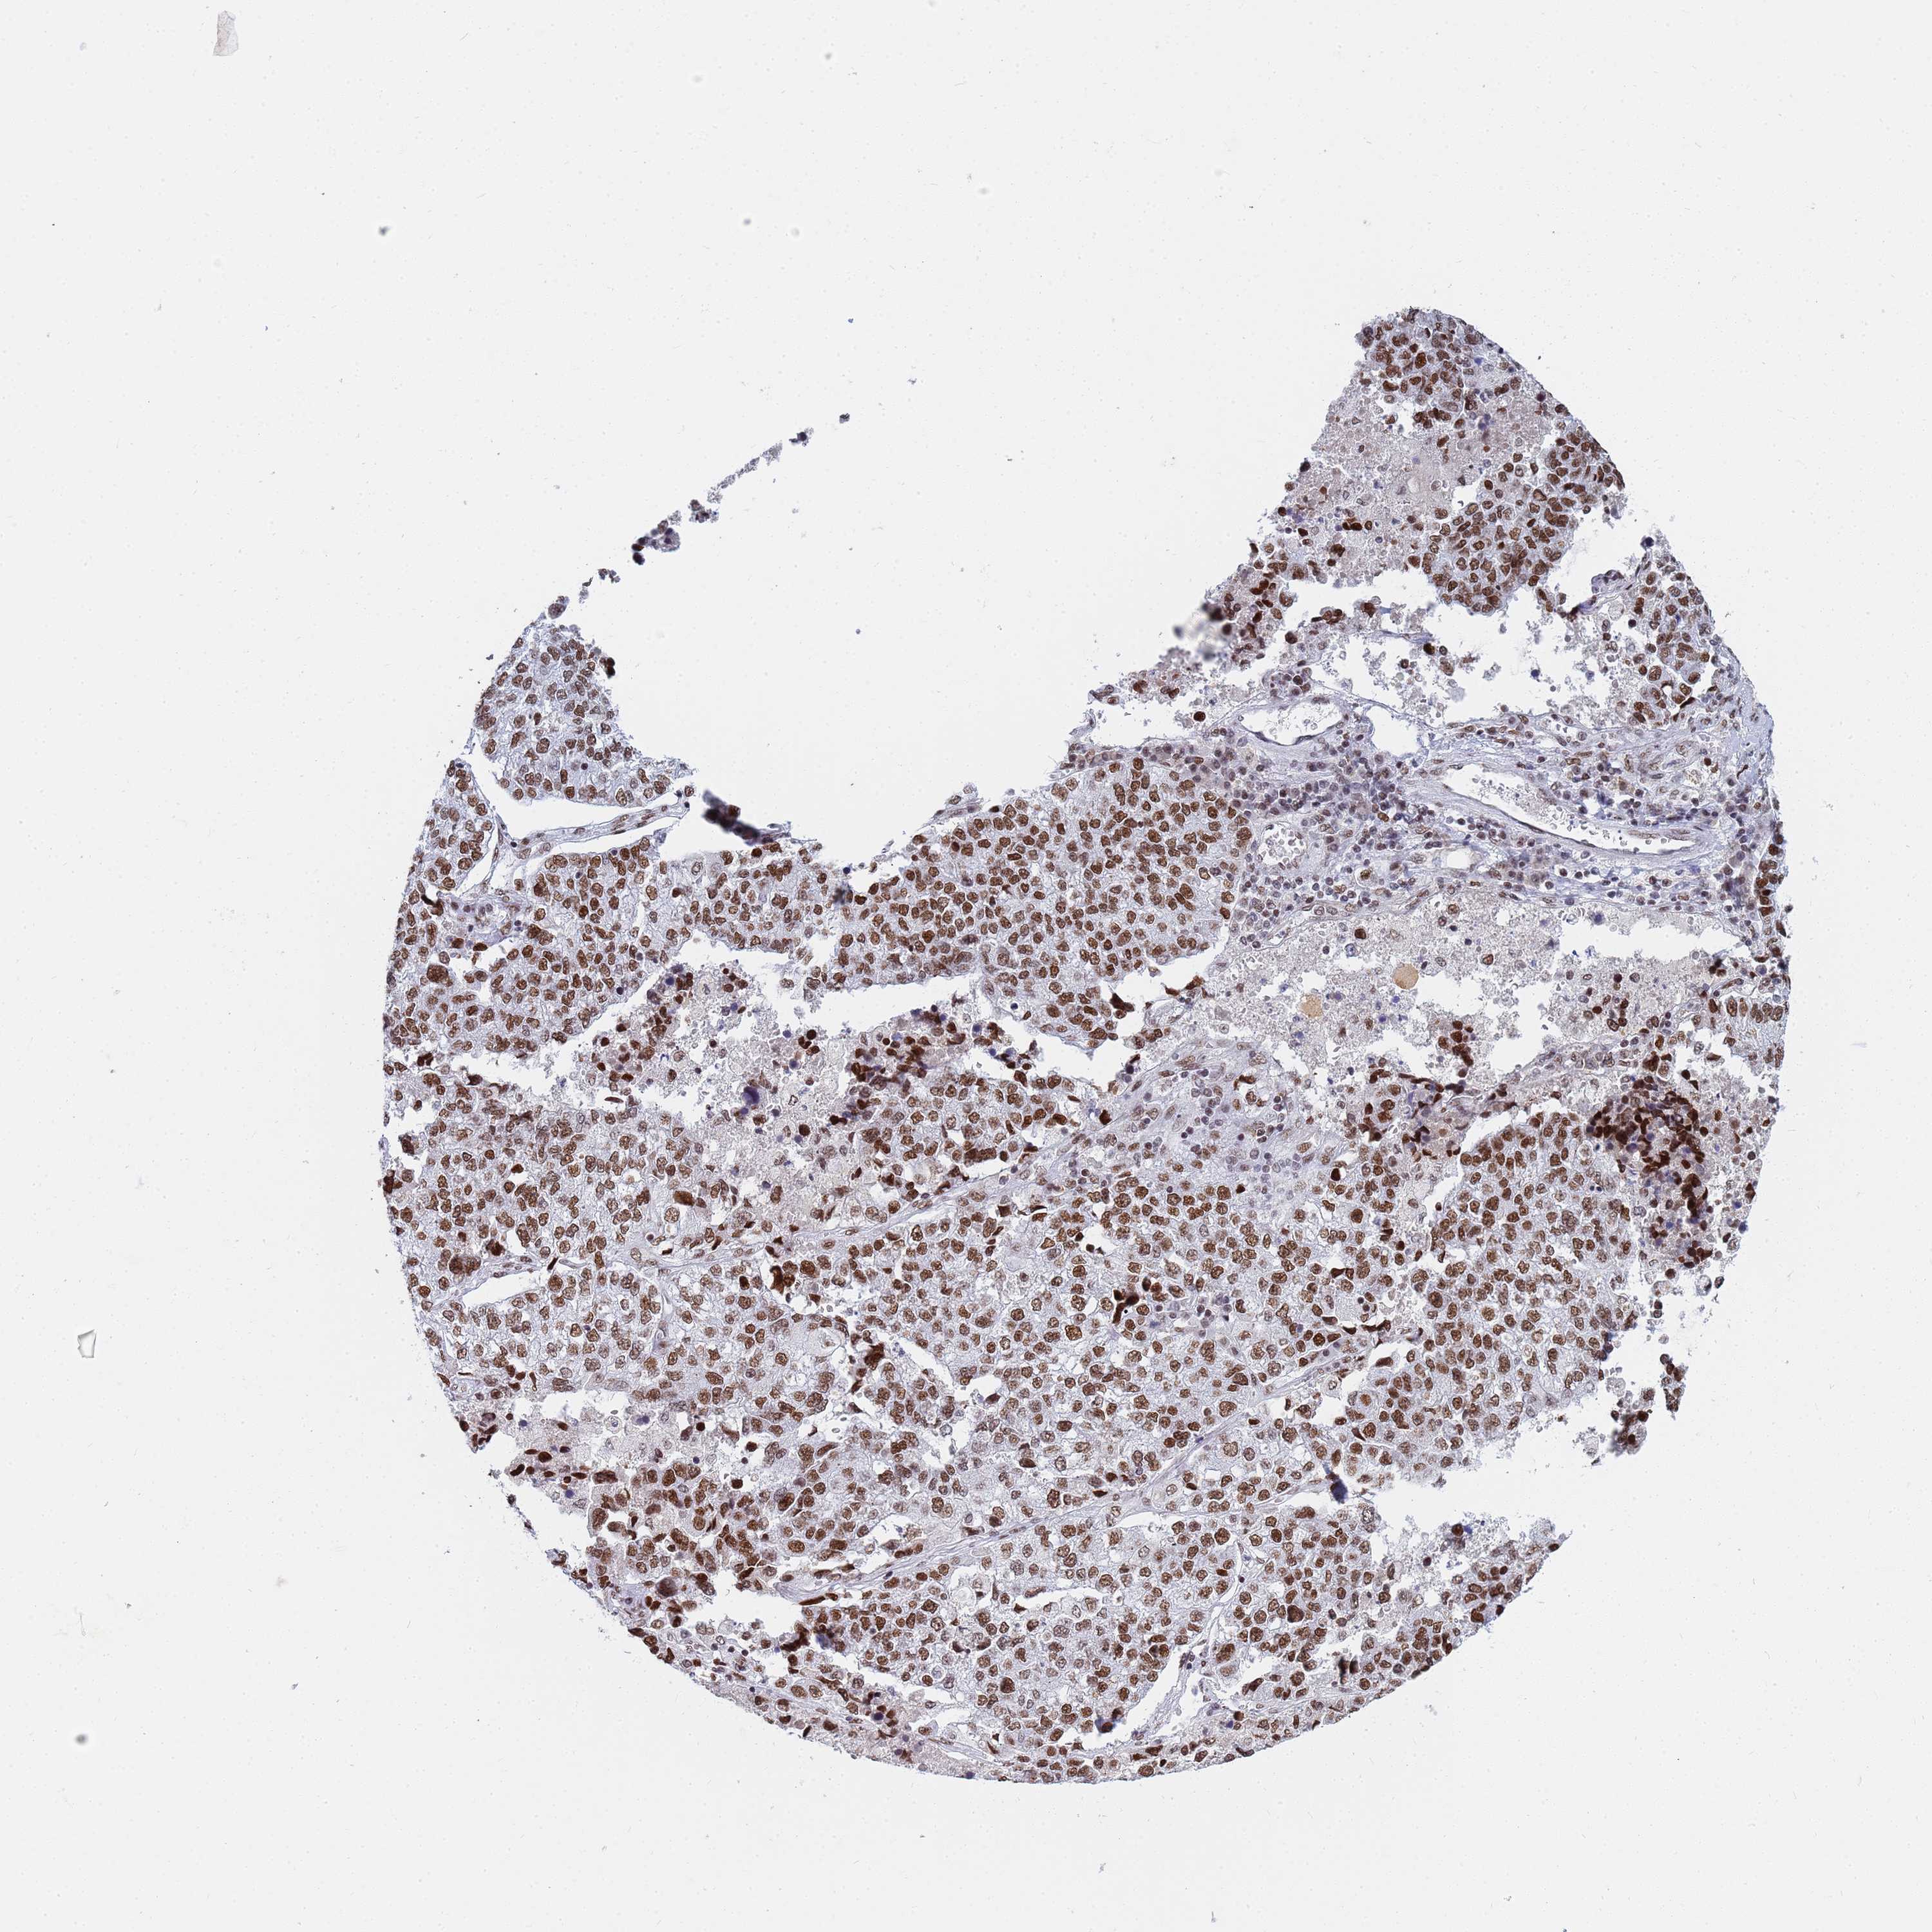

CANCER LUNG CANCER Show tissue menu